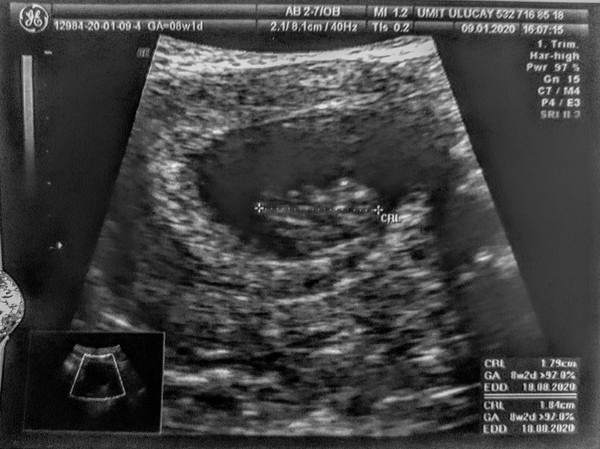

mrs87 · 27/01/2020 20:04

This is my ultrasound from Sunday, at 7+6. Was done transvaginally, can see baby and yolk sac! Heart beating 😊